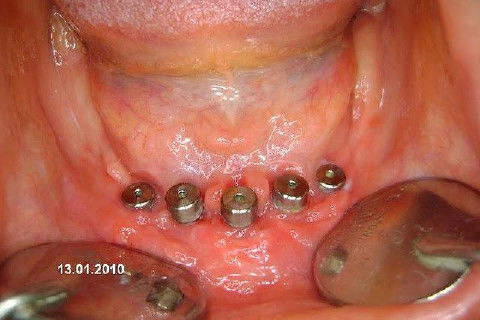

Protocolo Inferior com 5 Implantes - Parte I - Planejamento + Cirurgia

Apesar da boa adaptação e estética satisfatória, a principal queixa da paciente era a instabilidade da prótese inferior, como sempre ocorre nestes casos...atrofia do rebordo alveolar e perda da função mastigatória.